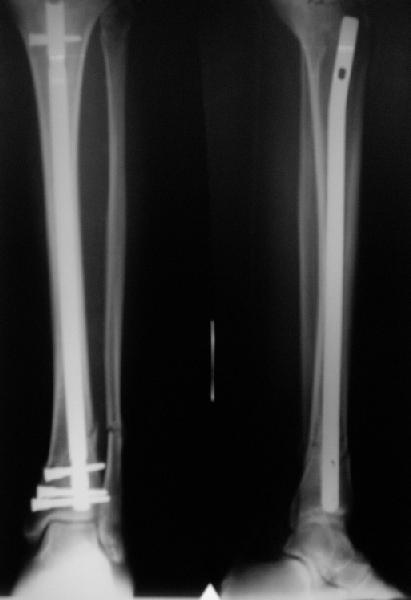

There are some more tricks which allow not to plate the fibula and provide good alignment and stability. A small wire distractor can provide alignment and restore length of both tibia and

fibula. Angular stability of the tibia is provided by insertion of more than two conventional medial-lateral locking screws. To maintain the position of the fibula perQ insertion of a single position screw often could be enough. I bet the articles didn't analyze the options.

A typical case is attached, also an image with intra-op reduction obtained by a small wire distractor, in the moment of insertion a Poller wire in AP direction. Fixation by a SIGN nail. Despite the fibula was not fixed healing was obtained with the unchanged alignment.